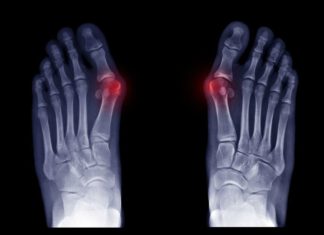

Five Reasons Your Big Toe Might Hurt

Is your big toe hurting? Experiencing discomfort in your foot can be incredibly frustrating, preventing you from walking and impacting your day-to-day life. Despite their small size, toes play an incredibly important part in...